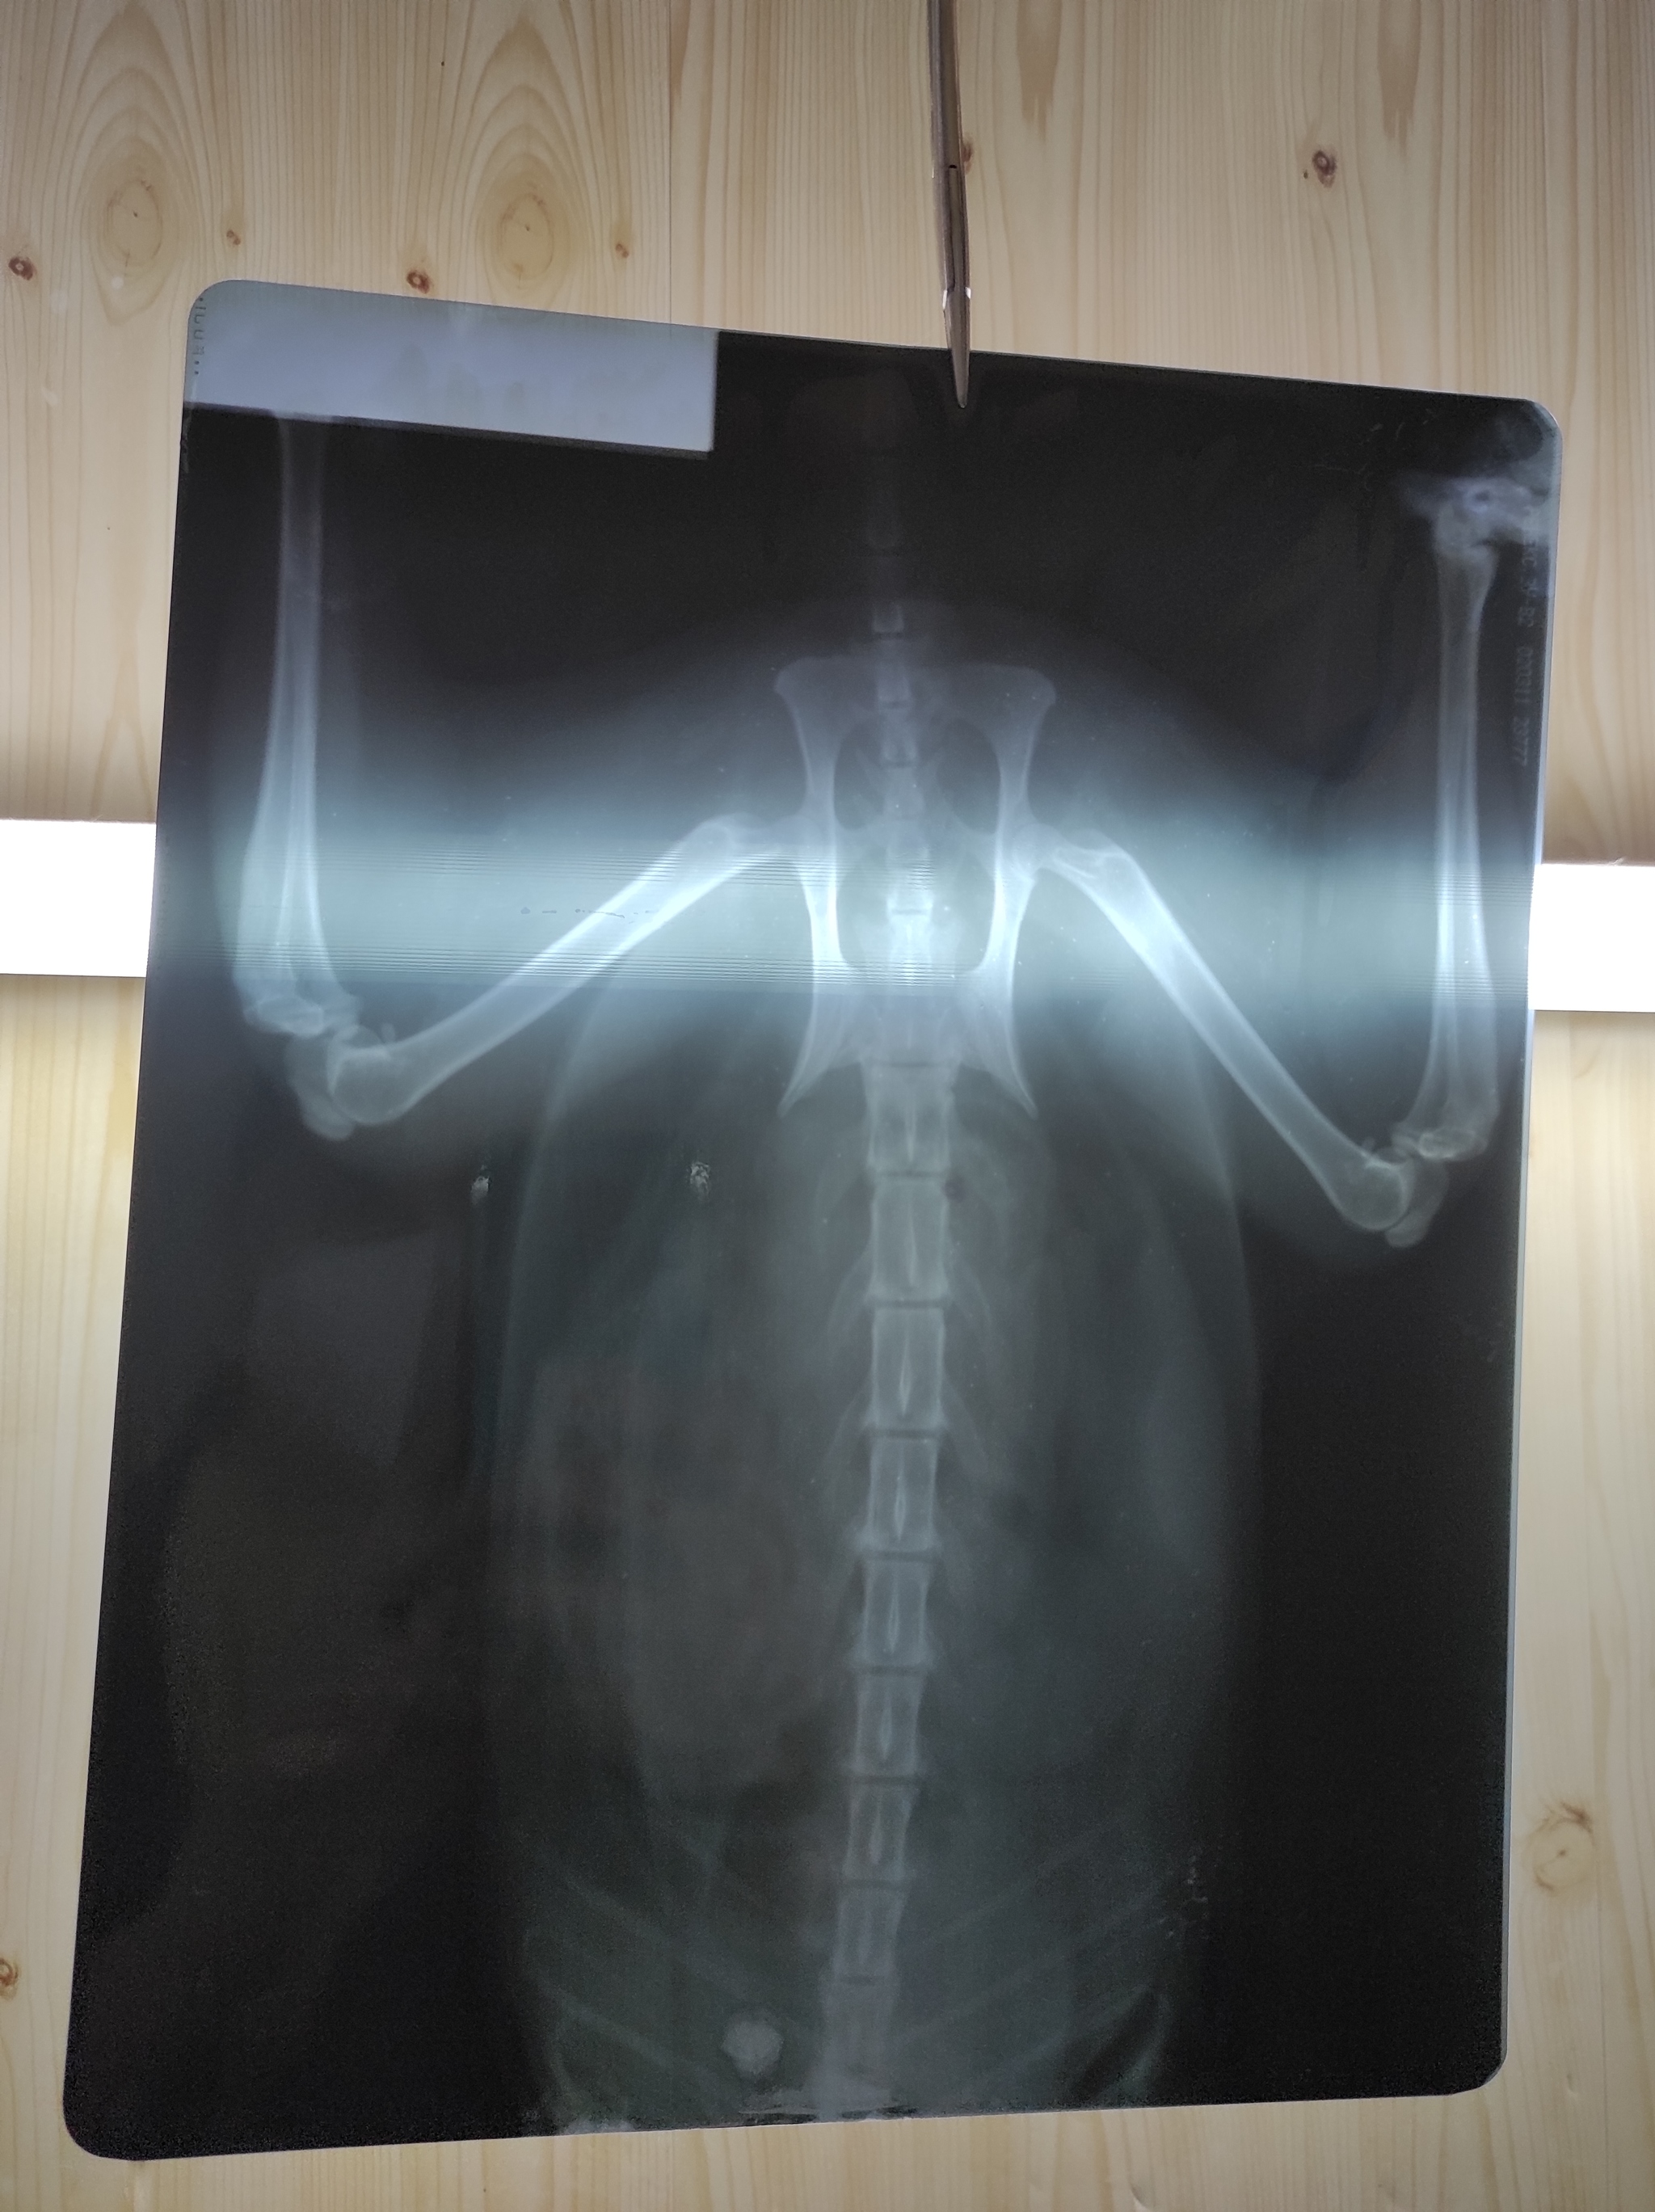

Только приехали от врачей. Помогал весь коллектив клиники. На рентгене видна гематома в месте удара, на животе синяк. Сломаны хрящи рëберные, немного воздуха под кожу вышло. Сделали тугую повязку, поставили уколы. Клетку для кроликов уже заказали, будет в ней жить ближайшее время. Состояние стабильное, прогнозы хорошие, а дальше видно будет.